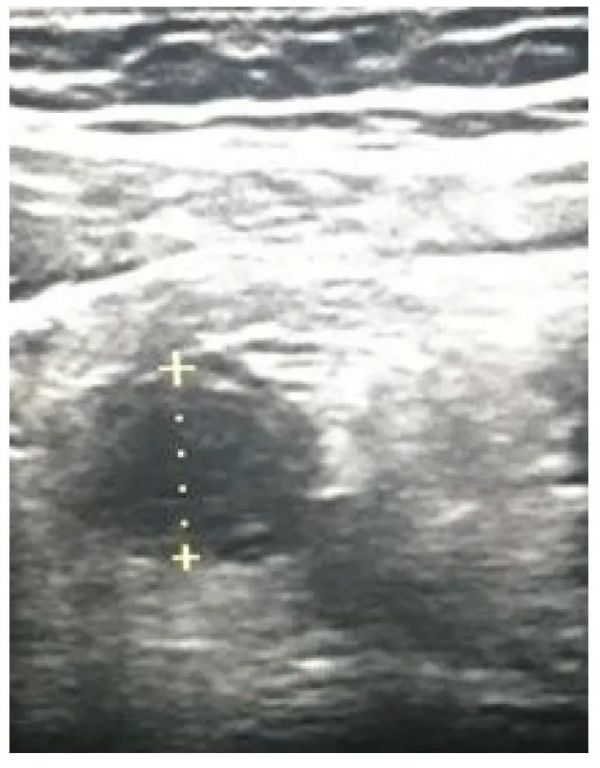

阑尾炎作为最常见的外科急症,每年的发生率为每100,000名成年人96.5-100例[134],高峰期在10-30岁之间,在两个极端年龄中均较少见[135]。阑尾炎的发生是由于阑尾腔阻塞,最常见的是阑尾、淋巴样增生或粪便嵌塞,而不太常见的病因是阑尾或盲肠肿瘤[135]。管腔梗阻可导致炎症、缺血、坏死,并可能随后出现阑尾穿孔[3]。大多数情况下,最初的症状是中肠周围的脐周绞痛,与腹膜的壁层刺激相吻合的聚集性局部疼痛[136],24小时内疼痛加重,伴有恶心、呕吐和食欲不振[137]。急性阑尾炎(图 5)是年轻患者急性腹症的最常见病因[138]。

图 5急性阑尾炎(阑尾直径11.9毫米)。

阑尾炎的诊断具有挑战性,需要综合临床、实验室和放射学发现[138]。如果未及时作出诊断,则可能发生穿孔和显著并发症[139]。如今,有证据表明,穿孔不一定是阑尾梗阻的必然结果,甚至这种消退也可能很常见[138]。多种影像学检查方式在急性阑尾炎的诊断中发挥着重要作用[18],由于其安全性,超声是所有年龄组的首选方式,尤其是儿童和孕妇[139,140,141]。POCUS由急诊科医生和医生进行,对阑尾炎的总体敏感性为91%[139]。一项meta分析显示,由急诊医生进行POCUS时,其敏感性为84%,特异性为91%,在儿童中的准确性更高[142]。阑尾的生理直径在4.4-5.1mm之间[143],而直径大于6mm则提示急性阑尾炎,同时伴有适当的临床表现[18]。Trout等人表明,阑尾直径为6-8 mm且大于8 mm在阑尾炎诊断中具有最高的准确度(分别为65%、96%),但如果阑尾直径小于6 mm,则只有2.6%的病例被诊断出阑尾炎[144]。阑尾炎的直接超声体征是一种不可压缩的肾小管结构,其目标体征在阑尾部位的直径大于6毫米(图 6)、阑尾石和多普勒超声检查的血管增多[18]。除这些体征外,还可以检测到阑尾周围的游离液体、脓肿形成、肠系膜脂肪回声性增加、局部肠系膜淋巴结肿大和壁增厚[18,140]。